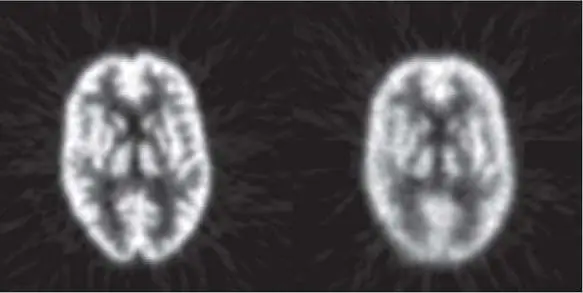

如圖所示,左圖影像較清晰, 右圖因某些原因造成影像變模糊,下列何者最不適當?FWHM最好小於 FWHM的 1/3linearity phantom )量測 MTF模組化的腦切片假體 (a model of slice of brain)右圖因某些原因造成影像變模糊 ,下列何者為最可能的原因下列何者為最可能的原因 ?

- 左圖:為一張正常且清晰的腦部橫切面核醫斷層影像(如腦部血流灌注 SPECT 或 FDG PET),可見大腦皮質(cerebral cortex)與深部灰質結構(如基底核 basal ganglia)邊界分明,空間解析度良好,解剖結構對稱且未見變形。

- 右圖:影像整體出現明顯的模糊(blurring)與空間解析度下降。除了邊界變得不清晰外,部分皮質結構出現方向性的輪廓暈開與形狀扭曲(smearing),此種失去邊緣銳利度且伴隨結構些微位移的特徵,高度提示為掃描過程中因位移所造成的假影。

- (A) 掃描時患者移動:患者在造影過程中若發生移動(patient motion),會導致不同投影角度擷取到的資料無法完美對齊,在重組後的影像上會呈現邊緣模糊、結構暈開或出現雙重輪廓(double contour),與右圖特徵最為吻合。